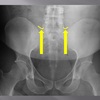

AP LUMBOPELVIC LANDMARKS A-P lumbopelvic view

110

superior iliac crests

A-P lumbopelvic view

112

ischial tuberosities

114

pubic/pubic symphysis

116

lateral aspect of sacrum

118

obturator foramen

120

supeiror endplate tips